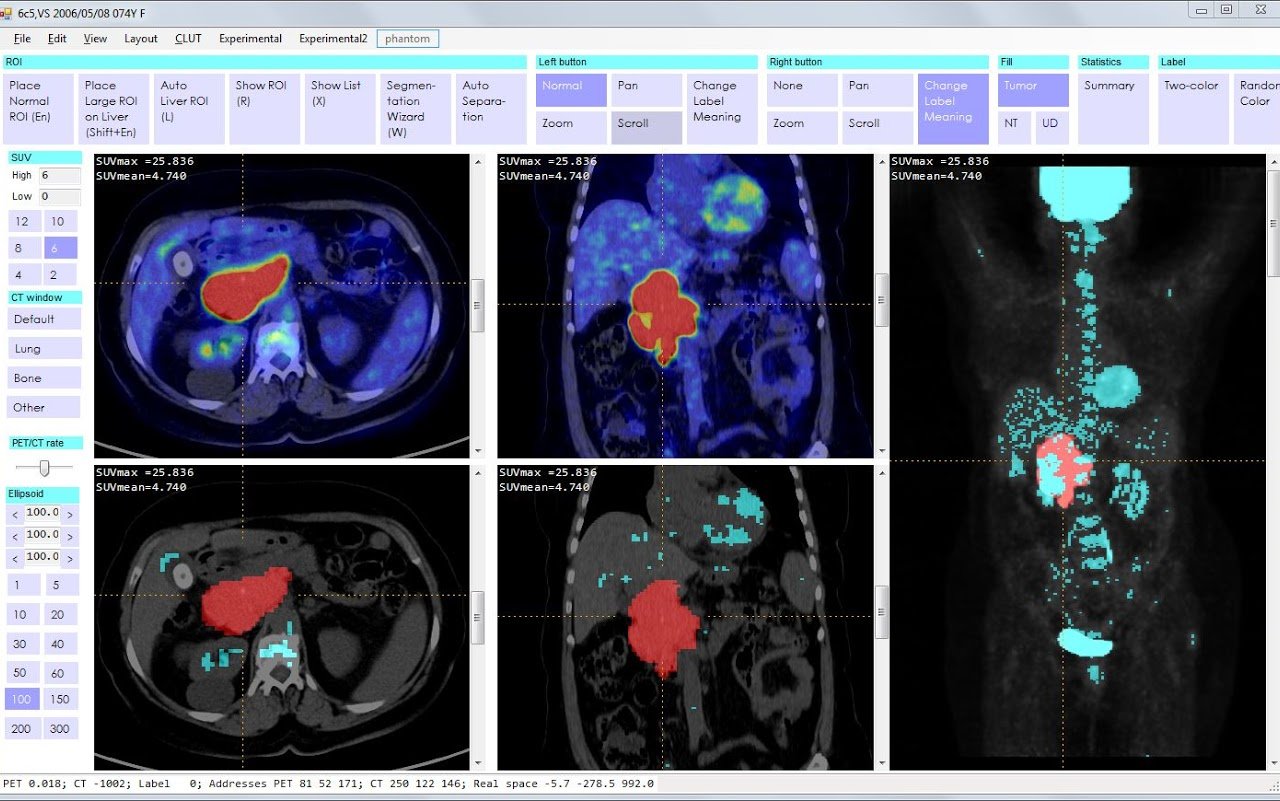

Nuclear Imaging

track a path of a radioactive tracer

Positron Emission Tomography

PET

allow to identify normal and abnormal activity in living tissue

SPECT and PET

functional chemical changes

typically metabolic activities

both use radioactive tracers

usually combined with CT scan